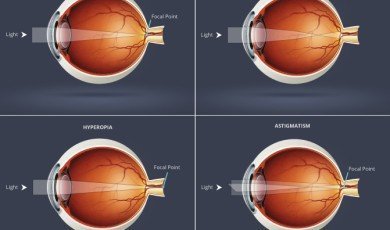

Refractive Errors

Refractive error means that the shape of...